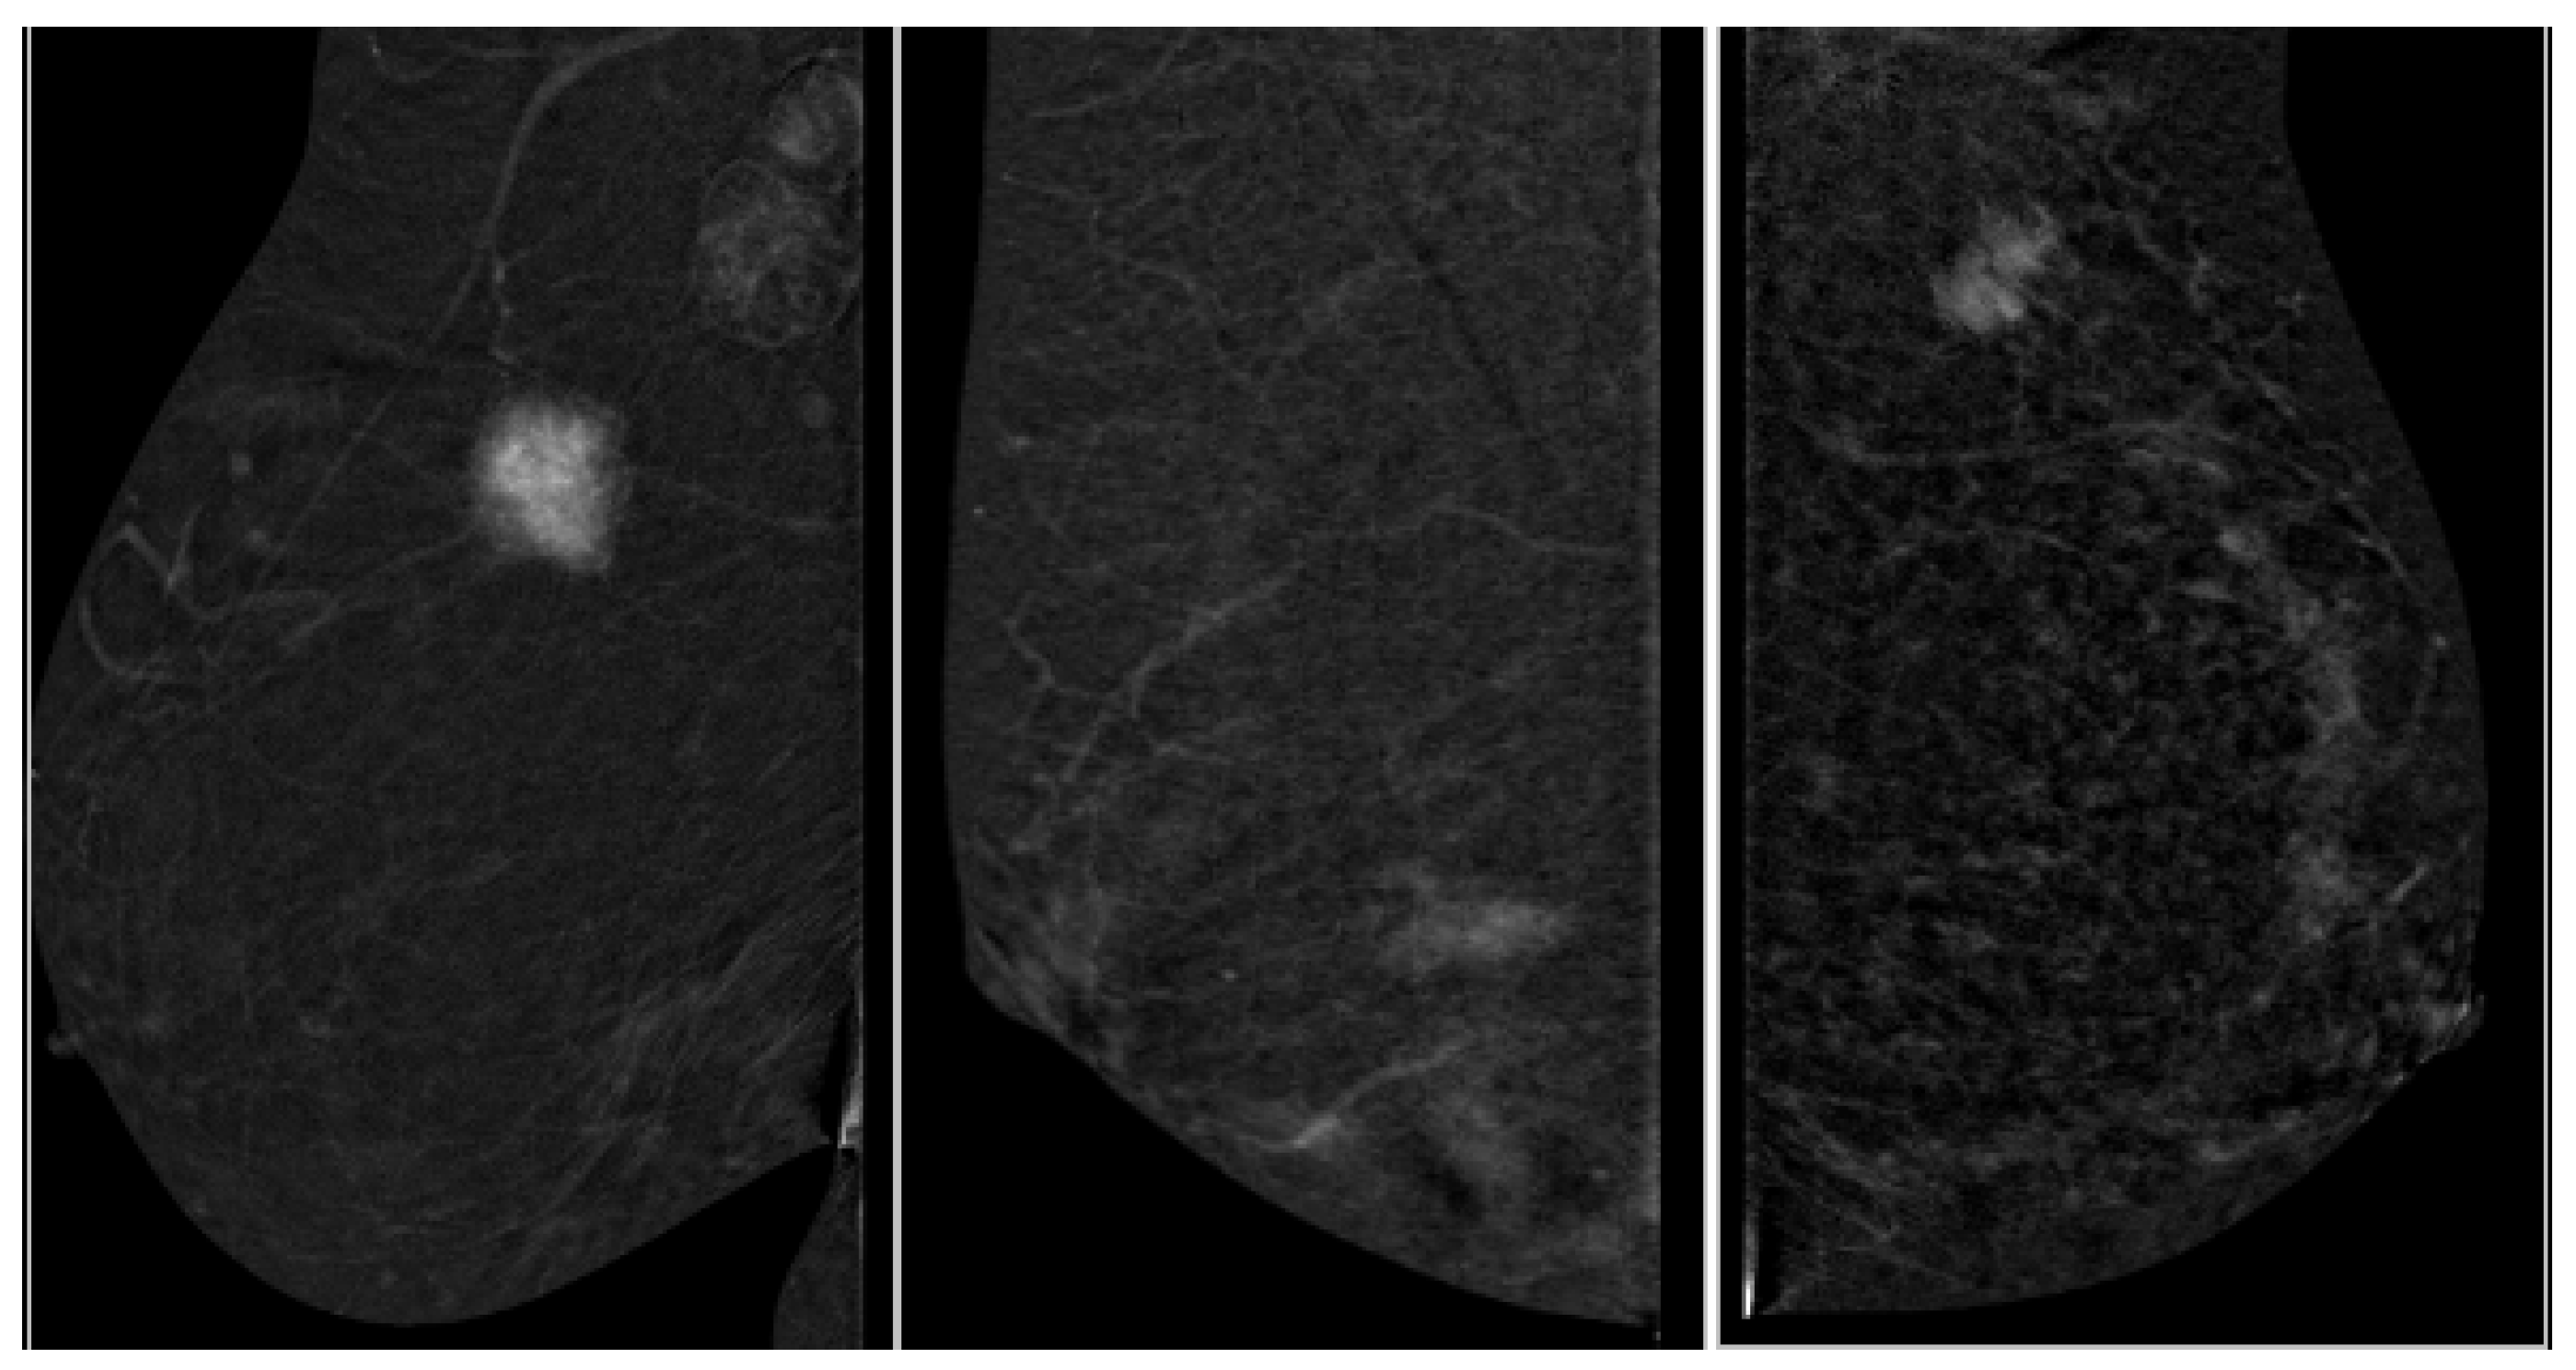

2.4. Image Analysis

- Enhancement intensity: high, moderate, low (visual signal relative to parenchyma),

- Enhancement homogeneity: homogeneous vs. heterogeneous (uniformity of contrast distribution).